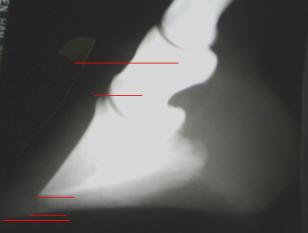

Fig. 3) Cadaver with severe distal displacement. In this particular cadaver the top of the coronet is actually level with the center of the second phalanx. With this pathological bone position (I should say hoof capsule position, as the bones are exactly where they should be. It is the entire hoof capsule that is truly displaced), it is impossible for the horse to enjoy a naturally short hoof and a thick sole at the same time.

Added 2010: This measurement is now in common use as the CE (coronet to extensor process) measurement.

Important note added in '08:

Notice how steep the coronary groove/proximal end of the hoof wall are. Also

notice that the inner proximal corner of the hoof wall is in the exact

perfect position it should be at the base of the extensor process. In

digital lateral radiographs we can clearly see this shape of the proximal

end of the hoof wall and its position on P3. Typically a case like this is

quick and easy to reverse. The proximal end of the hoof wall simply relaxes

to a lower angle; the laminae and coronary papillae do not actually have to move. However, if you

see the inner corner of the proximal end of the hoof wall (at the

lamellar/coronary junction) is displaced from the base of the extensor

process, the case will tend to be far more difficult to

rehabilitate/reverse. Do-able, but never 'smooth'.